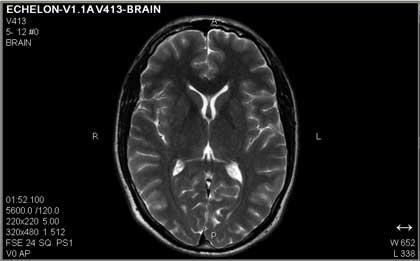

การตรวจสมองด้วยคลื่นแม่เหล็กไฟฟ้า (MRI Brain)

การตรวจคลื่นไฟฟ้าสมอง หรือ EEG นั้น จะเป็นตัวบ่งถึงสัญญาณไฟฟ้าที่ผิดปกติว่ามาจากบริเวณไหน และความถี่ของการกระจายของไฟฟ้าส่วนหนึ่งเท่านั้น แต่ EEG จะไม่สามารถบอกถึงพยาธิสภาพได้ ซึ่งในปัจจุบันทางศูนย์ฯ ได้นำ MRI Brain มาใช้ประกอบในการตรวจวินิจฉัย ประโยชน์ของ MRI Brain คือ ช่วยในการยืนยันพยาธิสภาพหลังจากตรวจ EEG แล้วว่า รอยโรคเป็นชนิดอะไร ซึ่งถ้าเราพบว่า พยาธิสภาพที่กระตุ้นให้เกิดอาการชักเกิดจากเนื้องอก หลอดเลือดผิดปกติ การรักษาก็จะไม่ใช้ยาเพียงอย่างเดียว แต่ต้องอาศัยการผ่าตัดเข้ามาประกอบด้วย